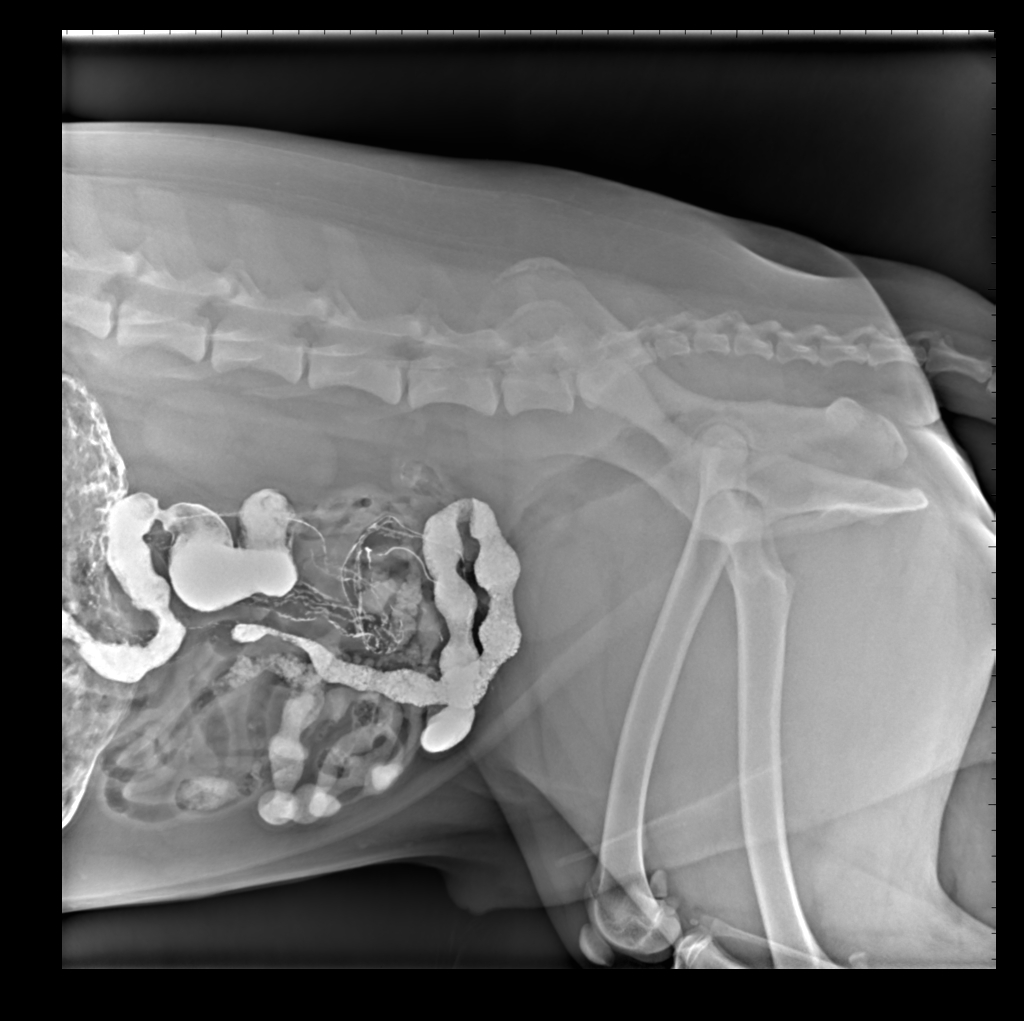

胃肠造影显示回肠盲肠升结肠横结肠侧位片